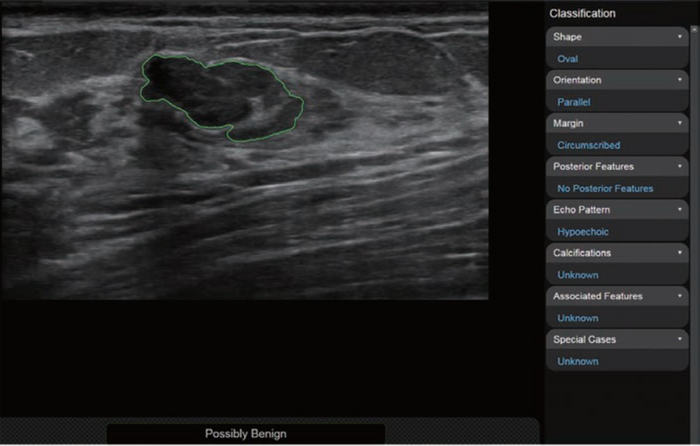

Leesburg, VA, May 17, 2023 According to an accepted manuscript published in ARRS’ own American Journal of Roentgenology ( AJR ) , deep learning–based computer-aided diagnosis (CAD) for breast lesion classification on ultrasound significantly improved radiologists’ diagnostic performance—particularly for reducing the frequency of benign breast biopsies.

Cui et al.’s AJR study included patients scheduled to undergo biopsy or surgical resection of a breast lesion, classified as BI-RADS category 3-5 on prior breast ultrasound, at eight Chinese secondary or rural hospitals from November 2021 to September 2022. Patients underwent an additional investigational breast ultrasound, both performed and interpreted by a radiologist with no expertise in the modality. Hybrid body-breast imagers—radiologists lacking breast subspecialty training or in whom breast ultrasound accounted for less than 10% of their ultrasounds performed annually—then assigned a BI-RADS category. CAD results were used to upgrade reader-assigned BI-RADS category 3 lesions to category 4A, as well as for downgrading BI-RADS 4A lesions to 3. Histologic results of biopsy or resection served as the researchers’ reference standard.

Ultimately, application of CAD to interpretations by radiologists without breast ultrasound expertise resulted in upgrade of 6.0% (6/100) of BI-RADS category 3 assessments to category 4A, of which 16.7% (1/6) were malignant, and downgrade of 79.1% (87/110) of category 4A assessments to category 3, of which 4.6% (4/87) were malignant.